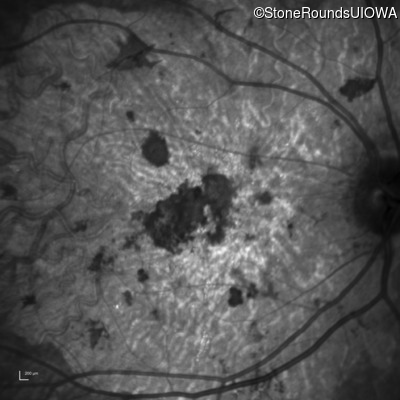

Infrared Fundus Photograph - Right - 20/200 sc

Exemplar